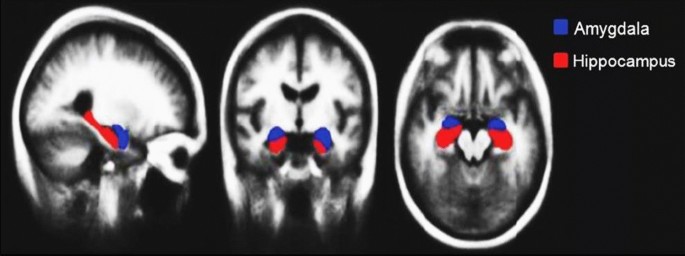

Hippocampus and amygdala region fusion: this step is done using the FSL visualization tool, based on Harvard Oxford subcortical structure, as shown in Fig. 1. The region fusion is calculated using the Fslmath command to add up the extracted hippocampus to the extracted amygdala so that to form one ROI, then it is treated as a new region which will be named Hippo-Amygdala ROI later to be analyzed.

The Hippocampus and Amygdala are considered the utmost smitten part in terms of shape by Alzheimer’s retrograding)6,13,20. Adding up the hippocampus important role associated with long-term memory, which includes all bygone awareness, and experiences21,22,23. Whereas, the Amygdala plays a pivotal function in the emotional processing such as: memory associated with emotions, and emotional stimuli adaptive responses24. Thus, finding new biomarkers is changing our understanding of AD, especially zooming out on these regions associated with cognitive impairment of patients, which might be confirming them to be potential target regions of treatment in AD. Otherwise, the existing challenge for modern neuroimaging is to help diagnose early AD and MCI patients. This will reflect the disease stage as well as the predictive progression of mild cognitive.